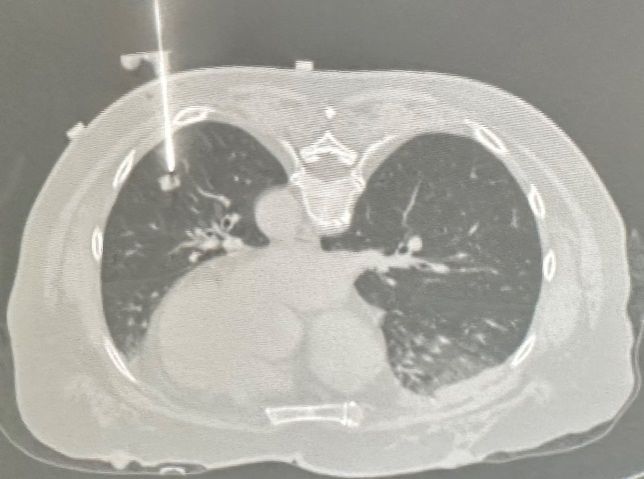

本次完成的两例手术均体现出机器人辅助穿刺的系统优势:患者一为乳腺癌新辅助治疗中,左肺下叶存在10mm微小结节;患者二为右肺下叶后基底段15mm结节。术前通过CT扫描于体表放置定位标记,系统自动识别并重建肺部三维模型,医生据此规划穿刺路径。术中,机器人机械臂在光学导航引导下精准定位,辅助术者将同轴穿刺针一次到位。CT复查确认针尖抵达目标病灶,活检取材满意。两例手术均仅耗时约十分钟,术后仅见少量肺内出血,未发生气胸等并发症,患者无明显不适。

目前,CT引导下的肺肿瘤消融、结节定位及穿刺活检等技术的核心均在于穿刺精度。传统方式高度依赖术者经验,常需多次扫描调针,时间长、辐射多,并发症风险较高。而机器人穿刺导航系统可精准复现规划路径,通过机械臂稳定操作,显著提升首次穿刺成功率,减少血管损伤,缩短手术时间,降低并发症发生率,为提高诊断符合率提供了可靠保障。该系统尤其适用于微小结节、解剖位置特殊(如肋骨遮挡、邻近重要血管及气道)以及下肺病灶的穿刺与消融治疗,有力支持了高难度病灶的精准诊疗。